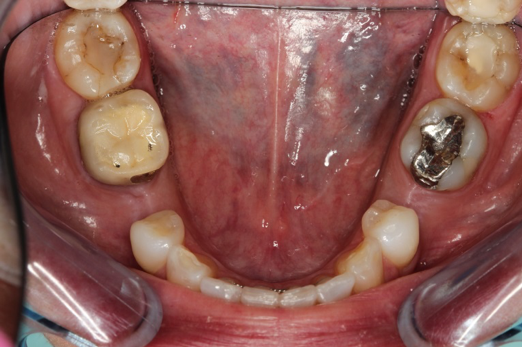

Fig 11. Preoperative healed sites.

Figure 11

Figure 10 through Figure 13 show the preoperative x-ray and the sequence of beginning with healed sites through the surgical placement of the implants. The implants were protected by an Essix-style wound-protection removable retainer for approximately 12 weeks. After the integration phase, the implants and the natural dentition were prepared using traditional crown-and-bridge high-speed diamond and zirconia cutting burs to remove decay and existing restorative materials, to complete and refine the natural-tooth structures to receive full-crown coverage, and to prepare and refine gingival margins of the zirconia implants where needed.